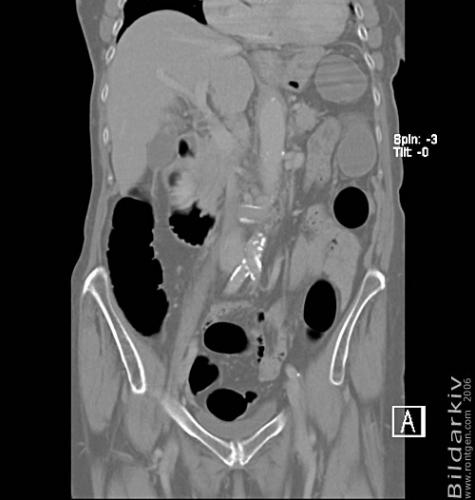

CT colon 25

Datortomografi av tjocktarmen (colon) med infunderad luft i tarmen samt med kontrast i blodbanan. Koronar bildserie.

CT multislice 16